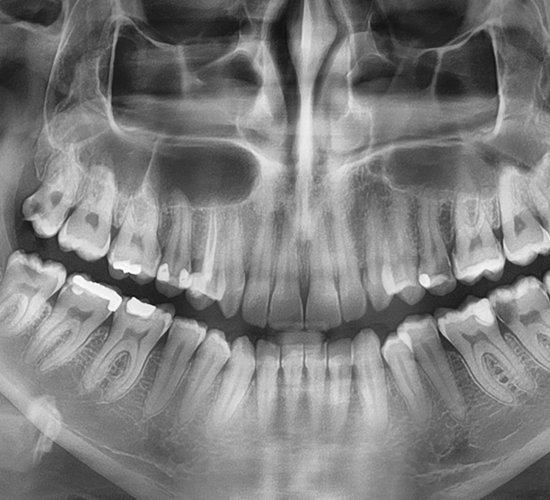

Radiografia dentară digitală este extrem de utilă în diagnosticarea unei afecțiuni dentare, oferindu-i medicului o unealtă extrem de precisă în detalii și măsurători pe baza cărora medicul poate evalua cantitatea și calitatea structurii osoase, poate vedea structuri anatomice precum nervii sau sinusurile maxilare.

Radiografia dentară intraorală periapicală prinde pe filmul digital întregul dinte de la coroană, până la rădăcină și țesuturile osoase de suport. Radiografia dentară periapicală ne ajută să identificăm anomalii la nivelul rădăcinii și a structurii osoase a dintelui.